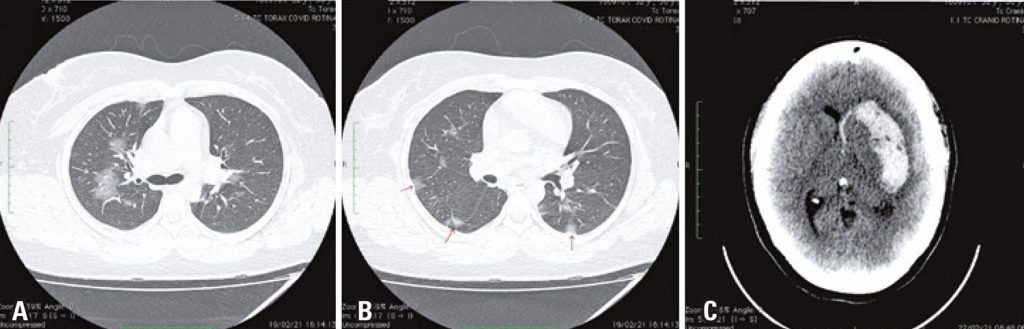

A 30-year-old woman had respiratory symptoms and a positive RT-PCR SARS-CoV-2 test. Chest computed tomography (CT) revealed 30-50% lung parenchymal involvement (), suggestive of viral pneumonia. Six days later, she presented with a thunderclap headache, right hemiplegia, and decreased consciousness. CT of the head revealed a large left parenchymal intracerebral hemorrhage (ICH) (), and the patient underwent a decompressive craniotomy. Cerebral angiography showed segmental narrowings followed by dilations in the V2 and V3 segments of the right and left vertebral arteries, suggesting bilateral vertebral artery dissection (VAD). No history of trauma or connective tissue disorders was noted. Furthermore, a mild segmental narrowing followed by a normal appearance in both the left posterior inferior cerebellar artery and distal branches of the left middle cerebral artery was observed, which, in this context, was suggestive of reversible cerebral vasoconstriction syndrome (RCVS) ( ). She had received corticosteroid therapy for COVID-19 and was not taking any anticoagulant or antiaggregant medications. She had a poor outcome and was classified with modified Rankin Scale 5 at discharge.